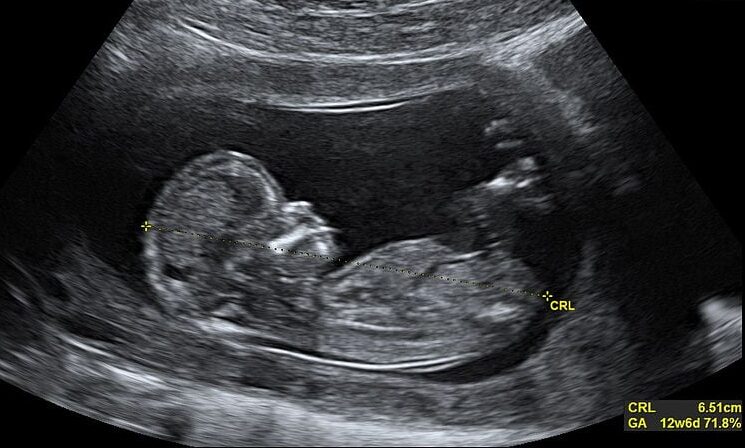

A Câmara de Vereadores de Maceió promulgou uma lei que prevê a obrigação de mulheres verem imagens de feto antes de realizarem um aborto legal. Além disso, elas também irão receber "orientações sobre riscos e as consequências" do aborto de equipes médicas. A lei foi publicada ontem, quarta-feira (20), no Diário Oficial do município.

A lei obriga apresentar, de forma detalhada e didática, "por meio de vídeos e imagens, os métodos cirúrgicos utilizados para executar o procedimento abortivo".